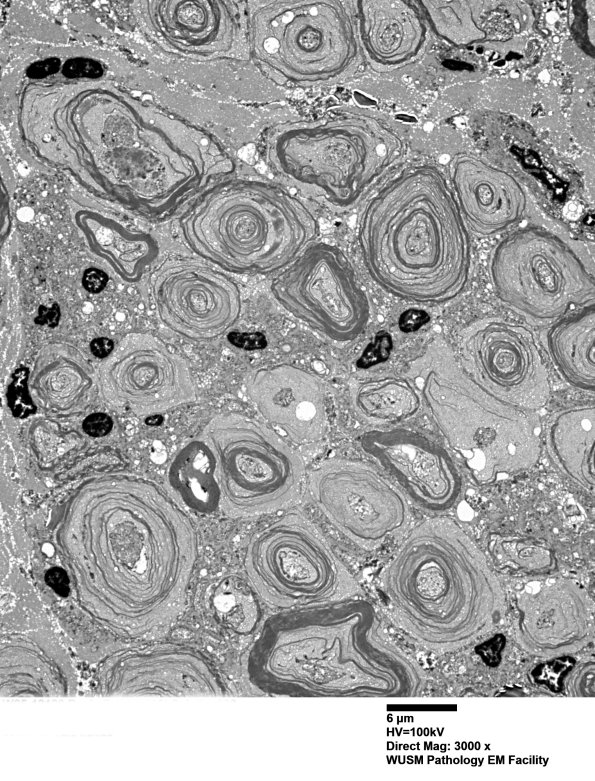

20E1,2 Most myelinated axons, large>small, are involved by vesicular myelin change. All axons show decomposition including unmyelinated axons. (electron micrographs)